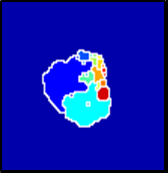

In MR images, tumor regions are normally brighter and have more uniform intensity than the neighbouring healthy tissue. Based on this fact, we determined the internal and external markers by sorting out the pixel values in ROIs in descending order and chose pixels with maximum intensity values as markers. After selecting the markers the normal watershed transformation is applied on the ROIs image which is shown in Fig 1 Finally, a binary mask is generated based on watershed output regions. However, we identified the optimal number of markers based on segmentation accuracy evaluated using Dice and Jaccard.

We tested the algorithm by varying the number of markers between and . Fig 2 describes the segmentation results obtained using different numbers of markers. This plot indicates that markers were found to be optimal using this segmentation approach, yielding satisfactory results.

where refers to the ROIs segmented by our algorithm and is tumor area as determined by manual segmentation. Table 1 summarizes the segmentation accuracy achieved using the proposed method for all 106 cases. The average dice coefficient was found to be 0.780.17 and average Jaccard index was 0.670.21. Fig 3 demonstrate four sample segmentation outputs which are overlaid on manual segmentations provided by two radiologists. It can be seen, that the proposed method could accurately segment the lesions with some marginal errors for medium to large tumors. However, for cases comprising disjoint lesions, the method failed to segment all small lesions and in some cases incorrectly labeled healthy tissue as lesions. This is because in some cases there is a high degree of overlap in the intensity distributions of healthy breast tissue and lesions, and the ROI drawn by the radiologist is very large in the case of disjoint lesions, in order to cover the entire area over which multiple lesions are distributed.